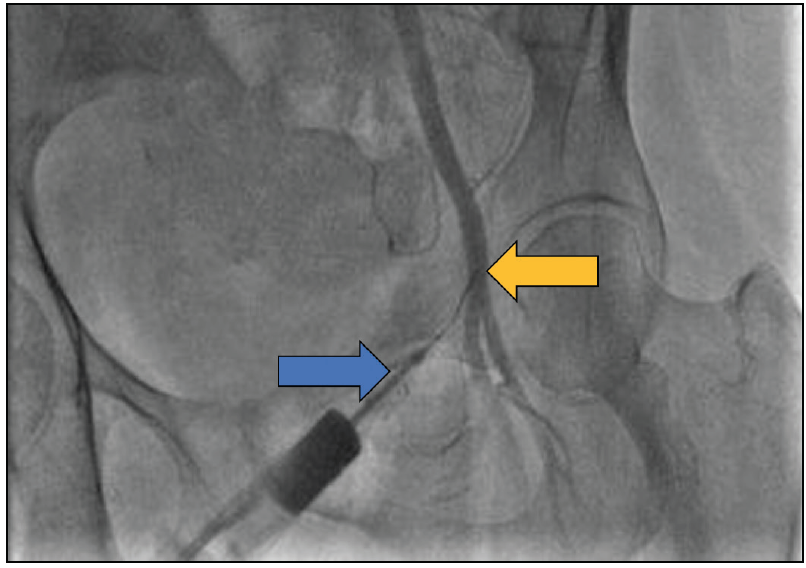

External Contralateral Bypass Circuit

If there is occlusion of the external iliac artery and common femoral artery by the large-bore sheath, the ipsilateral SFA is accessed via a 4- or 6-F sheath (with a micropuncture kit) in an antegrade fashion. Contralateral common femoral artery access is then obtained with a 6-F sheath. The side arm of the contralateral sheath is then connected to the side arm of the ipsilateral antegrade sheath using a male-to-male connector. The result is an external femoral-femoral bypass whereby blood flows from the contralateral 6-F sheath through the side arm into the side arm of the ipsilateral 4- to 6-F antegrade sheath down the ischemic limb providing adequate perfusion (Figures 3 and Figure 4). In situations when occlusion of flow is anticipated (eg, with an ECMO sheath), antegrade access can be secured preemptively prior to the large-bore sheath insertion. The target activated clotting time (ACT) should be longer than standard to maintain the flow (range, 200–220 seconds). Also, hourly serial Doppler ultrasound assessment of the lower extremity pulsations is recommended.

Figure 3. Right common femoral artery with a large-bore sheath in situ. In this case, the large-bore sheath was inserted for prolonged MSC and was occlusive to distal flow. An external contralateral conduit was created from the contralateral femoral artery. A 6-F sheath was used in the left common femoral artery, and through it, a 4-F, 45-cm-long catheter was advanced over a 0.035-inch hydrophilic stiff wire from the left common femoral artery into the right common femoral artery and beyond the large-bore access point. Then, the catheter and wire were further advanced to the SFA. The side arm of the “donor/mother” sheath and “recipient/daughter” catheter on the left side were connected using a male-to-male connector to create flow from the left to right femoral artery (dotted arrows).

Figure 4. Illustration of the contralateral bypass circuit for a large occlusive sheath in the right common femoral artery. Blood flows through the left 7-F sheath (blue arrow) to the 4-F daughter sheath (green arrow) and through the 45-cm catheter to the contralateral right side. The catheter then passes along the large-bore sheath (yellow arrow) and to the right SFA to bypass the occlusion and provide perfusion to the right leg.